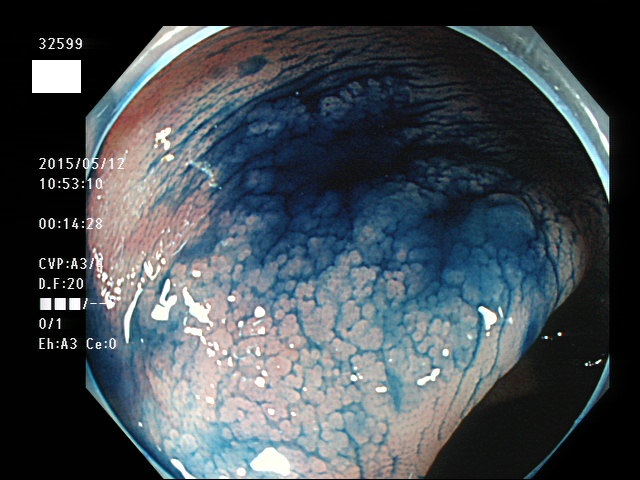

上記100名より抽出した平坦・陥凹型腺腫(=癌化の危険が高いが見落としやすい病変)の内視鏡写真

32595 32597 32599・・・・・・の63名